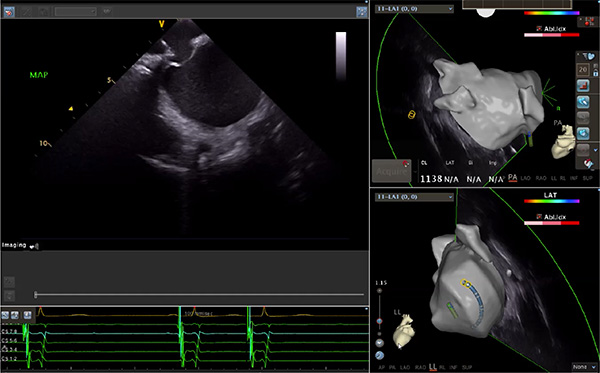

超聲心動(dòng)圖技術(shù)包括常規(guī)經(jīng)胸超聲(TTE)、經(jīng)食管超聲(TEE)、心腔內(nèi)超聲(ICE)、超聲聲學(xué)造影(MCE)、三維超聲心動(dòng)圖等,ICE是一種新興技術(shù)——將微型的換能器安裝在心導(dǎo)管的尖端,經(jīng)由外周血管輸送至心腔內(nèi)部,換能器發(fā)射聲波,對(duì)心臟及其鄰近組織進(jìn)行實(shí)時(shí)高質(zhì)量成像和(或)血流動(dòng)力學(xué)測(cè)定的超聲成像技術(shù)。基于不同的技術(shù)原理,心腔內(nèi)超聲導(dǎo)管被分為兩類:機(jī)械旋轉(zhuǎn)式超聲導(dǎo)管和相控陣超聲導(dǎo)管。目前,臨床上主要應(yīng)用的是相控陣超聲導(dǎo)管,ICE成像通過(guò)術(shù)者旋轉(zhuǎn)導(dǎo)管及操縱導(dǎo)管手柄上的兩個(gè)旋鈕來(lái)完成。

ICE門檻高、集成了超聲和圖像處理最前端的技術(shù),是當(dāng)前內(nèi)窺超聲方向最挑戰(zhàn)的領(lǐng)域。不同于傳統(tǒng)接觸式三維重建方法會(huì)產(chǎn)生假腔,影響術(shù)者對(duì)靶點(diǎn)或結(jié)構(gòu)的判斷,心腔內(nèi)超聲(ICE)可直接顯示心臟結(jié)構(gòu),有助于理解心臟內(nèi)各部位之間的解剖關(guān)系,不僅具有實(shí)時(shí)成像、并發(fā)癥監(jiān)測(cè)以及良好的耐受性,同時(shí)以股靜脈入路,無(wú)需全麻或深度鎮(zhèn)靜,日益成為心臟介入手術(shù)中重要輔助工具,被譽(yù)為心臟介入醫(yī)生的“黃金眼”。心腔內(nèi)超聲可用于多種心臟介入手術(shù),潛在患者群體龐大,動(dòng)脈網(wǎng)測(cè)算我國(guó)心腔內(nèi)超聲導(dǎo)管市場(chǎng)空間或?qū)⒊?00億元,具有廣闊前景。

隨著心腔內(nèi)超聲的應(yīng)用更廣,性能也在逐漸優(yōu)化,已從二維成像轉(zhuǎn)變?yōu)?strong>三維成像,極大增強(qiáng)了引導(dǎo)及可視化能力。二維心腔內(nèi)超聲支持雙平面或三平面成像,可顯示兩個(gè)或三個(gè)不同的平面視圖,但醫(yī)生需將這些圖像在腦海中重新構(gòu)建為三維解剖結(jié)構(gòu)。三維心腔內(nèi)超聲則可直接呈現(xiàn)三維解剖結(jié)構(gòu)圖,便于醫(yī)生更輕松地開(kāi)展手術(shù)。按照產(chǎn)品發(fā)展方向,預(yù)計(jì)心腔內(nèi)超聲還將向更清晰、精準(zhǔn)、多功能等方向發(fā)展。